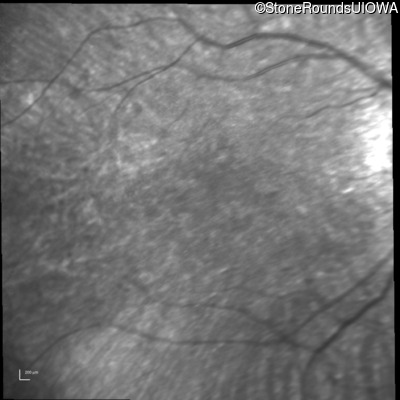

Infrared Fundus Photograph - Right - 20/80 -1

Exemplar